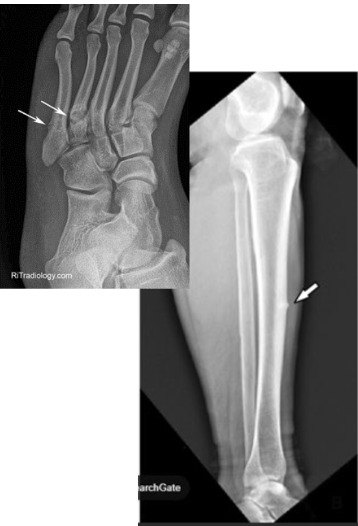

What type of fracture is this?

Avulsion

What is an avulsion fracture?

Fragment of bone is pulled away an attached tendon or ligament

Chip

What is a chip fracture?

Isolated bone fragment NOT caused by tendon or ligament